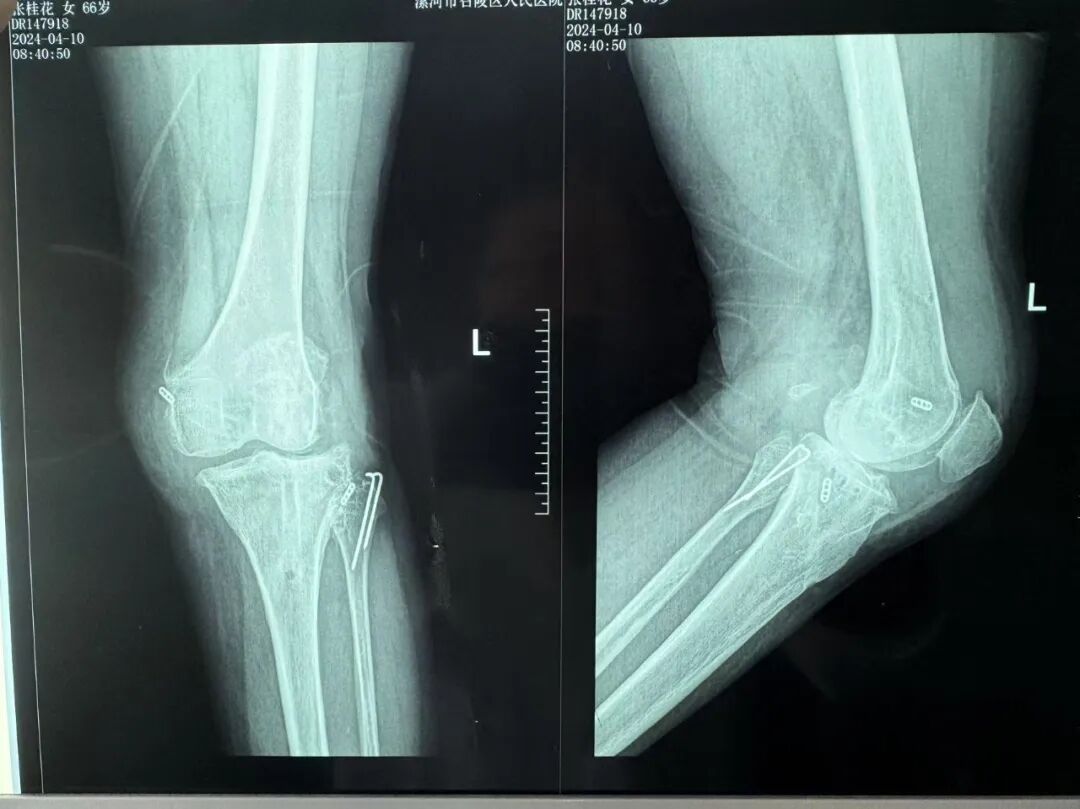

患者来院后,漯河市骨科医院(漯河医专二附院、漯河市立医院)主治医师康乐成了她的管床医生。经过详细的术前诊断与检查后,关节外科主任李付彬组织科室团队针对患者的诊断情况进行术前讨论。患者被诊断为重度膝关节骨关节炎,需要进行人工关节置换。但术前评估结果显示:患者膝关节侧方不稳定,单纯进行初次表面膝关节置换,术后仍会存在侧方不稳的情况,会影响术后效果以及假体使用年限,不仅无法完全恢复膝关节功能,还会加重患者的经济负担。

为了给患者带来更好的治疗效果,减轻其经济负担,经综合评估后,李付彬主任带领团队制定了最终的手术方案 —— 决定使用髁限制性膝关节假体(LCCK)置换膝关节。作为解决患者病痛的最优方案,这项手术的具体实施难度并不小,需要在术中根据截骨情况进行多次评估和实时调整,这就要求主刀医生不仅要具备过硬的专业技术与能力,还要能够结合自身经验准确判断、精准操作。

手术过程中,关节外科团队为患者进行了标准截骨。经过评估,患者膝关节仍存在侧方不稳定,便按照原定手术计划使用 LCCK 假体进行了膝关节置换。经过再次评估,患者膝关节稳定性恢复,下肢力线正常。这台高难度的 LCCK 膝关节置换手术在一小时内顺利完成!术后第二天,患者就能够自主下床负重活动,功能恢复良好。